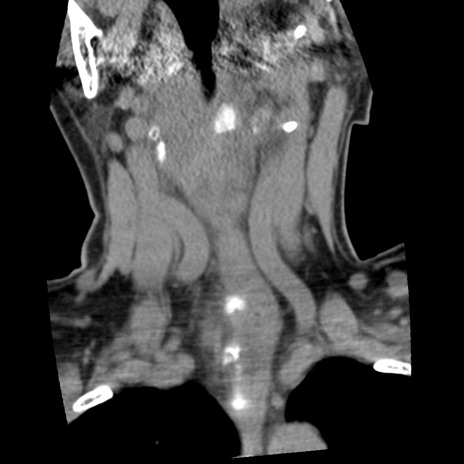

症例50 頚椎CT(冠状断像)

【症例】60歳代女性

【主訴】後頭部〜右後頸部にかけての痛み

【現病歴】本日飲食店でコーヒーを飲んでいたところ、突然後頭部〜右後頸部にかけて痛みが出現し、右上肢の感覚障害を伴ったため救急要請。

【身体所見】脳神経学的に明らかな異常所見を認めず。右上肢に軽度の感覚障害あり。

異常所見と診断は?

頚椎CT